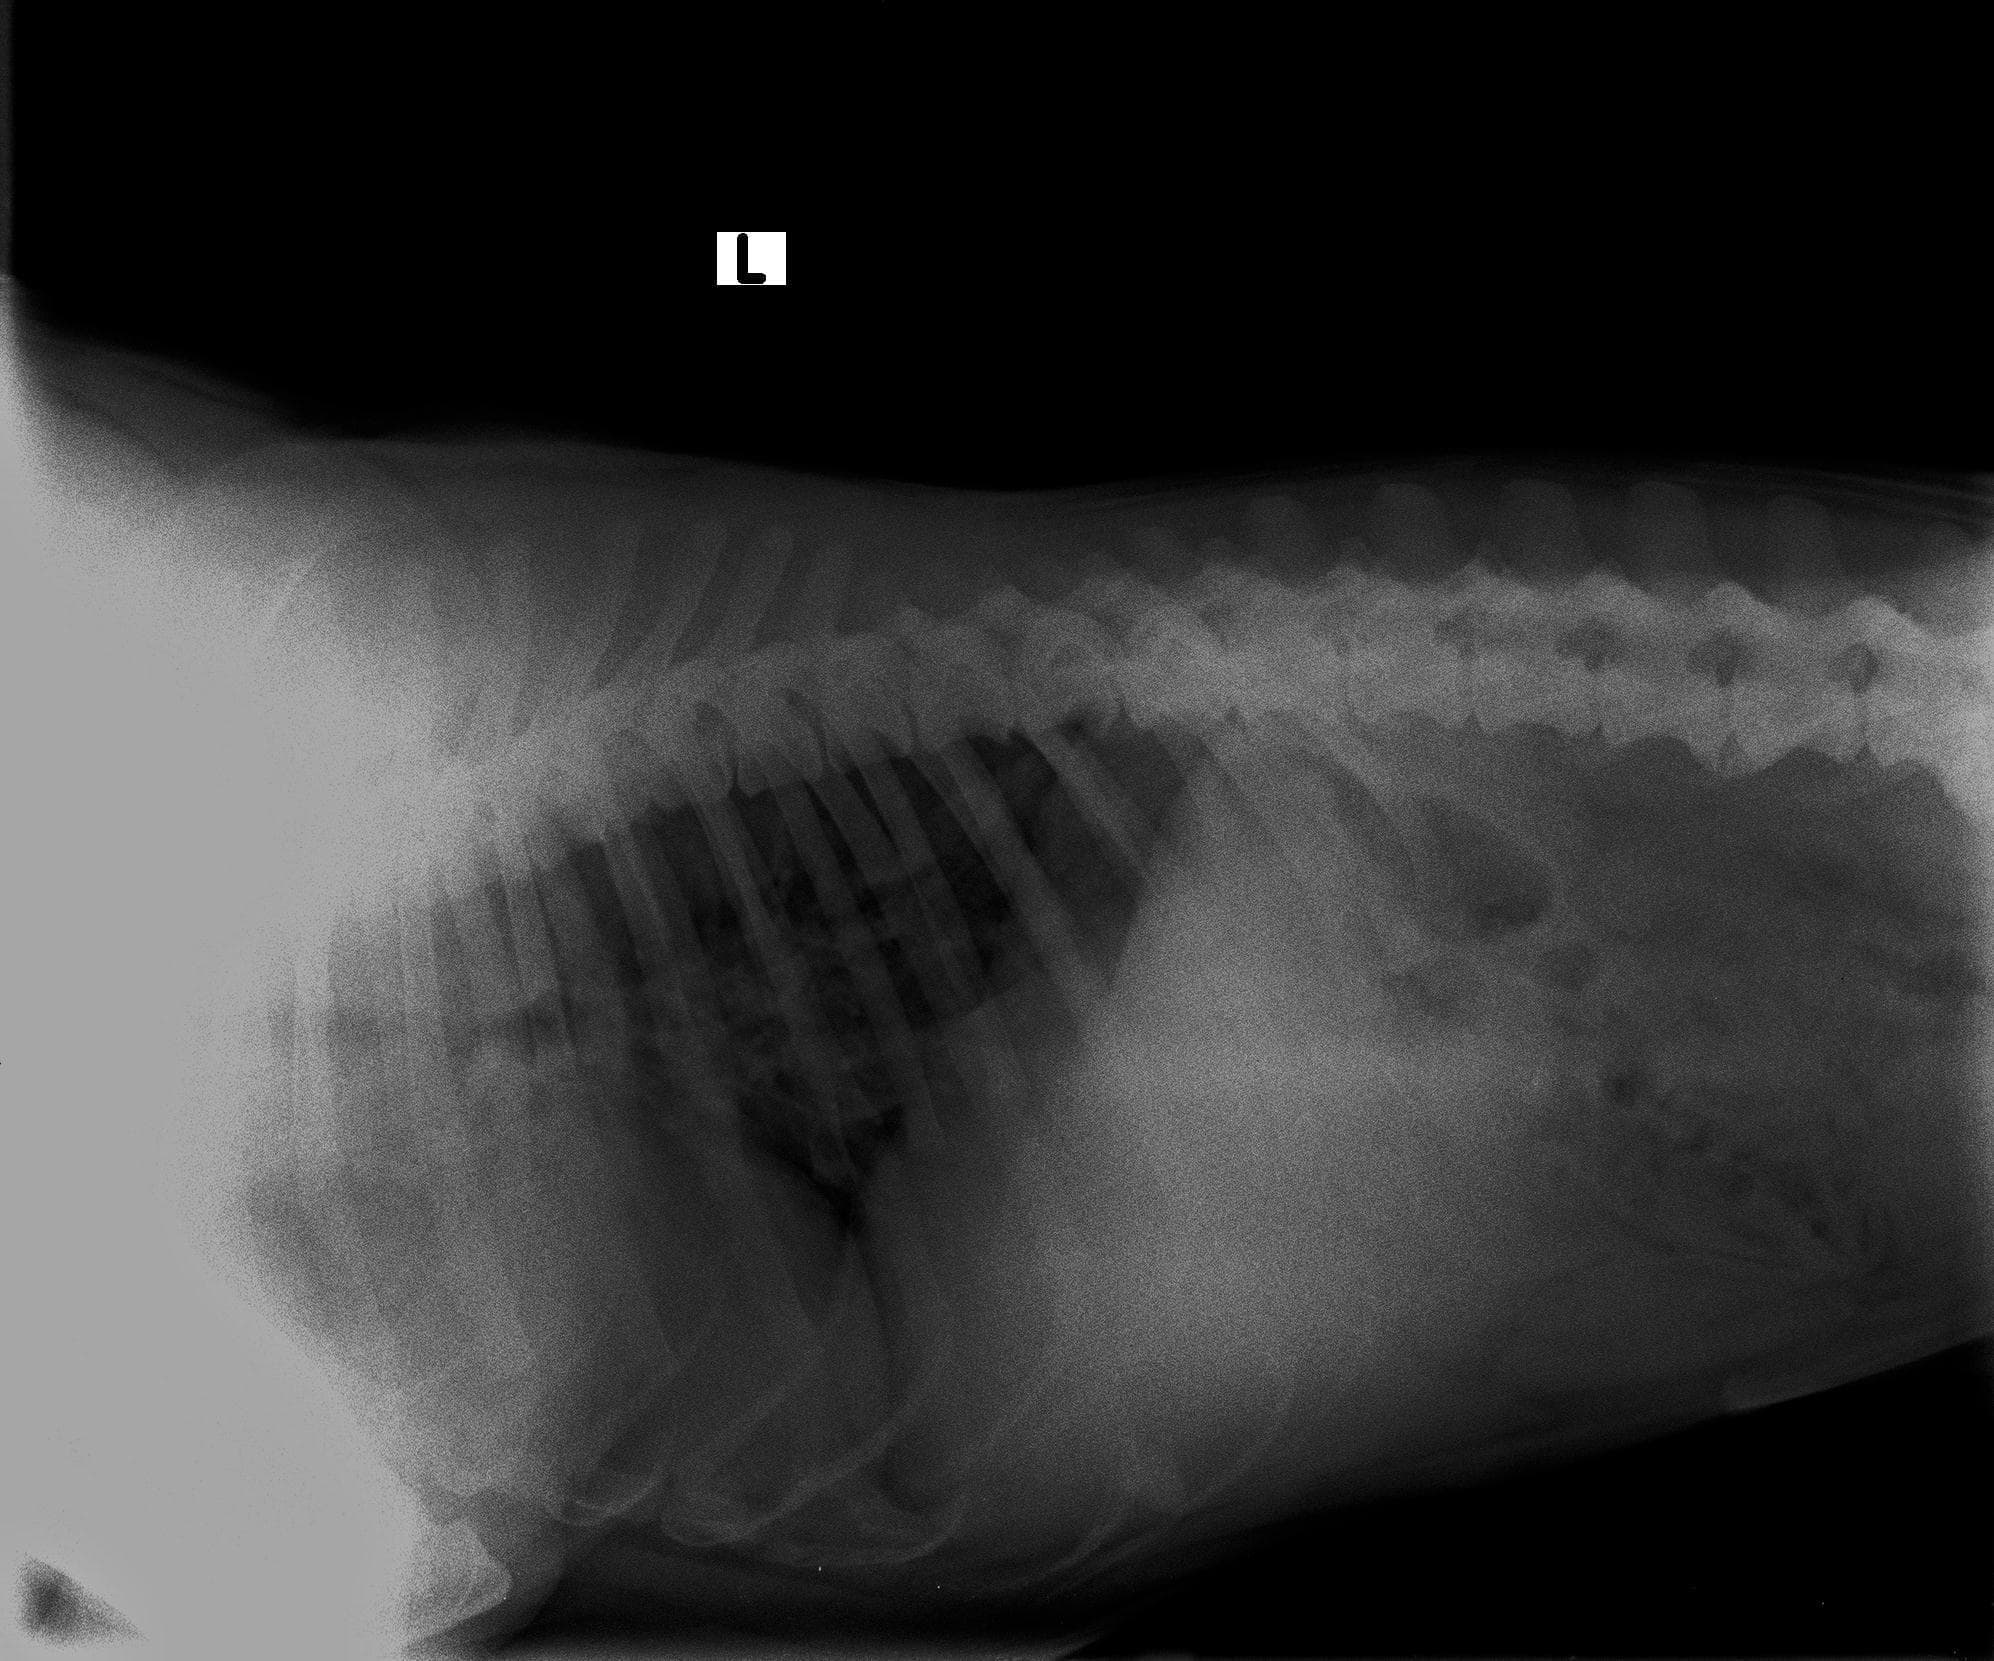

Hello, I am looking for a second though on my dogs bone conditions. She all of a sudden today couldn't walk. The pet accomodation messaged to tell.me this midday. I had her X rated and apparently she has both Hip Dysplasia and Spondylosis. 1. From the phoso of each can you indicate level of severity in each case and how long they potentially been present for? 2. Indicate which of the two is causing her not to walk Thank you

Hello and thank you for contacting Petco Pet Education Center, formerly Petcoach. There is severe hip dysplasia present in both hips, I am afraid. The left hip id also subluxated and I suspect it is causing more discomfort than the right hip. Hip dysplasia is a disease that dogs are born with. Arya must have had it sine a puppy but most likely it was not as severe as now. Spondylosis in the lumbar spine is usually a result of infection of intervertebral disc. Typically, it is an accidental finding in dogs that do not cause mobility problems. However, CT scan of the spine would give more detailed information about the severity of spondylosis.